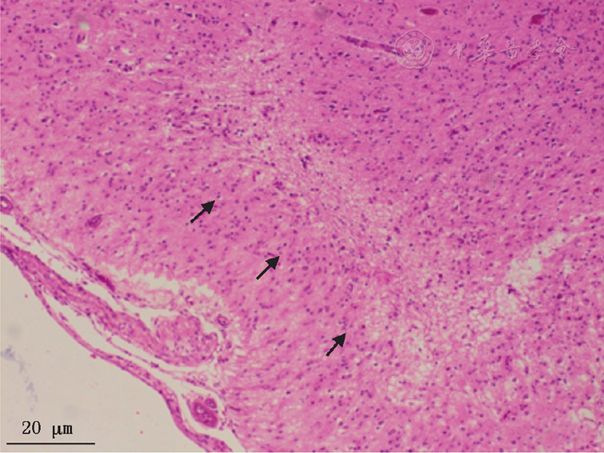

毛细血管以及星形胶质细胞增生(箭头)he染色不同类型的线粒体病可以